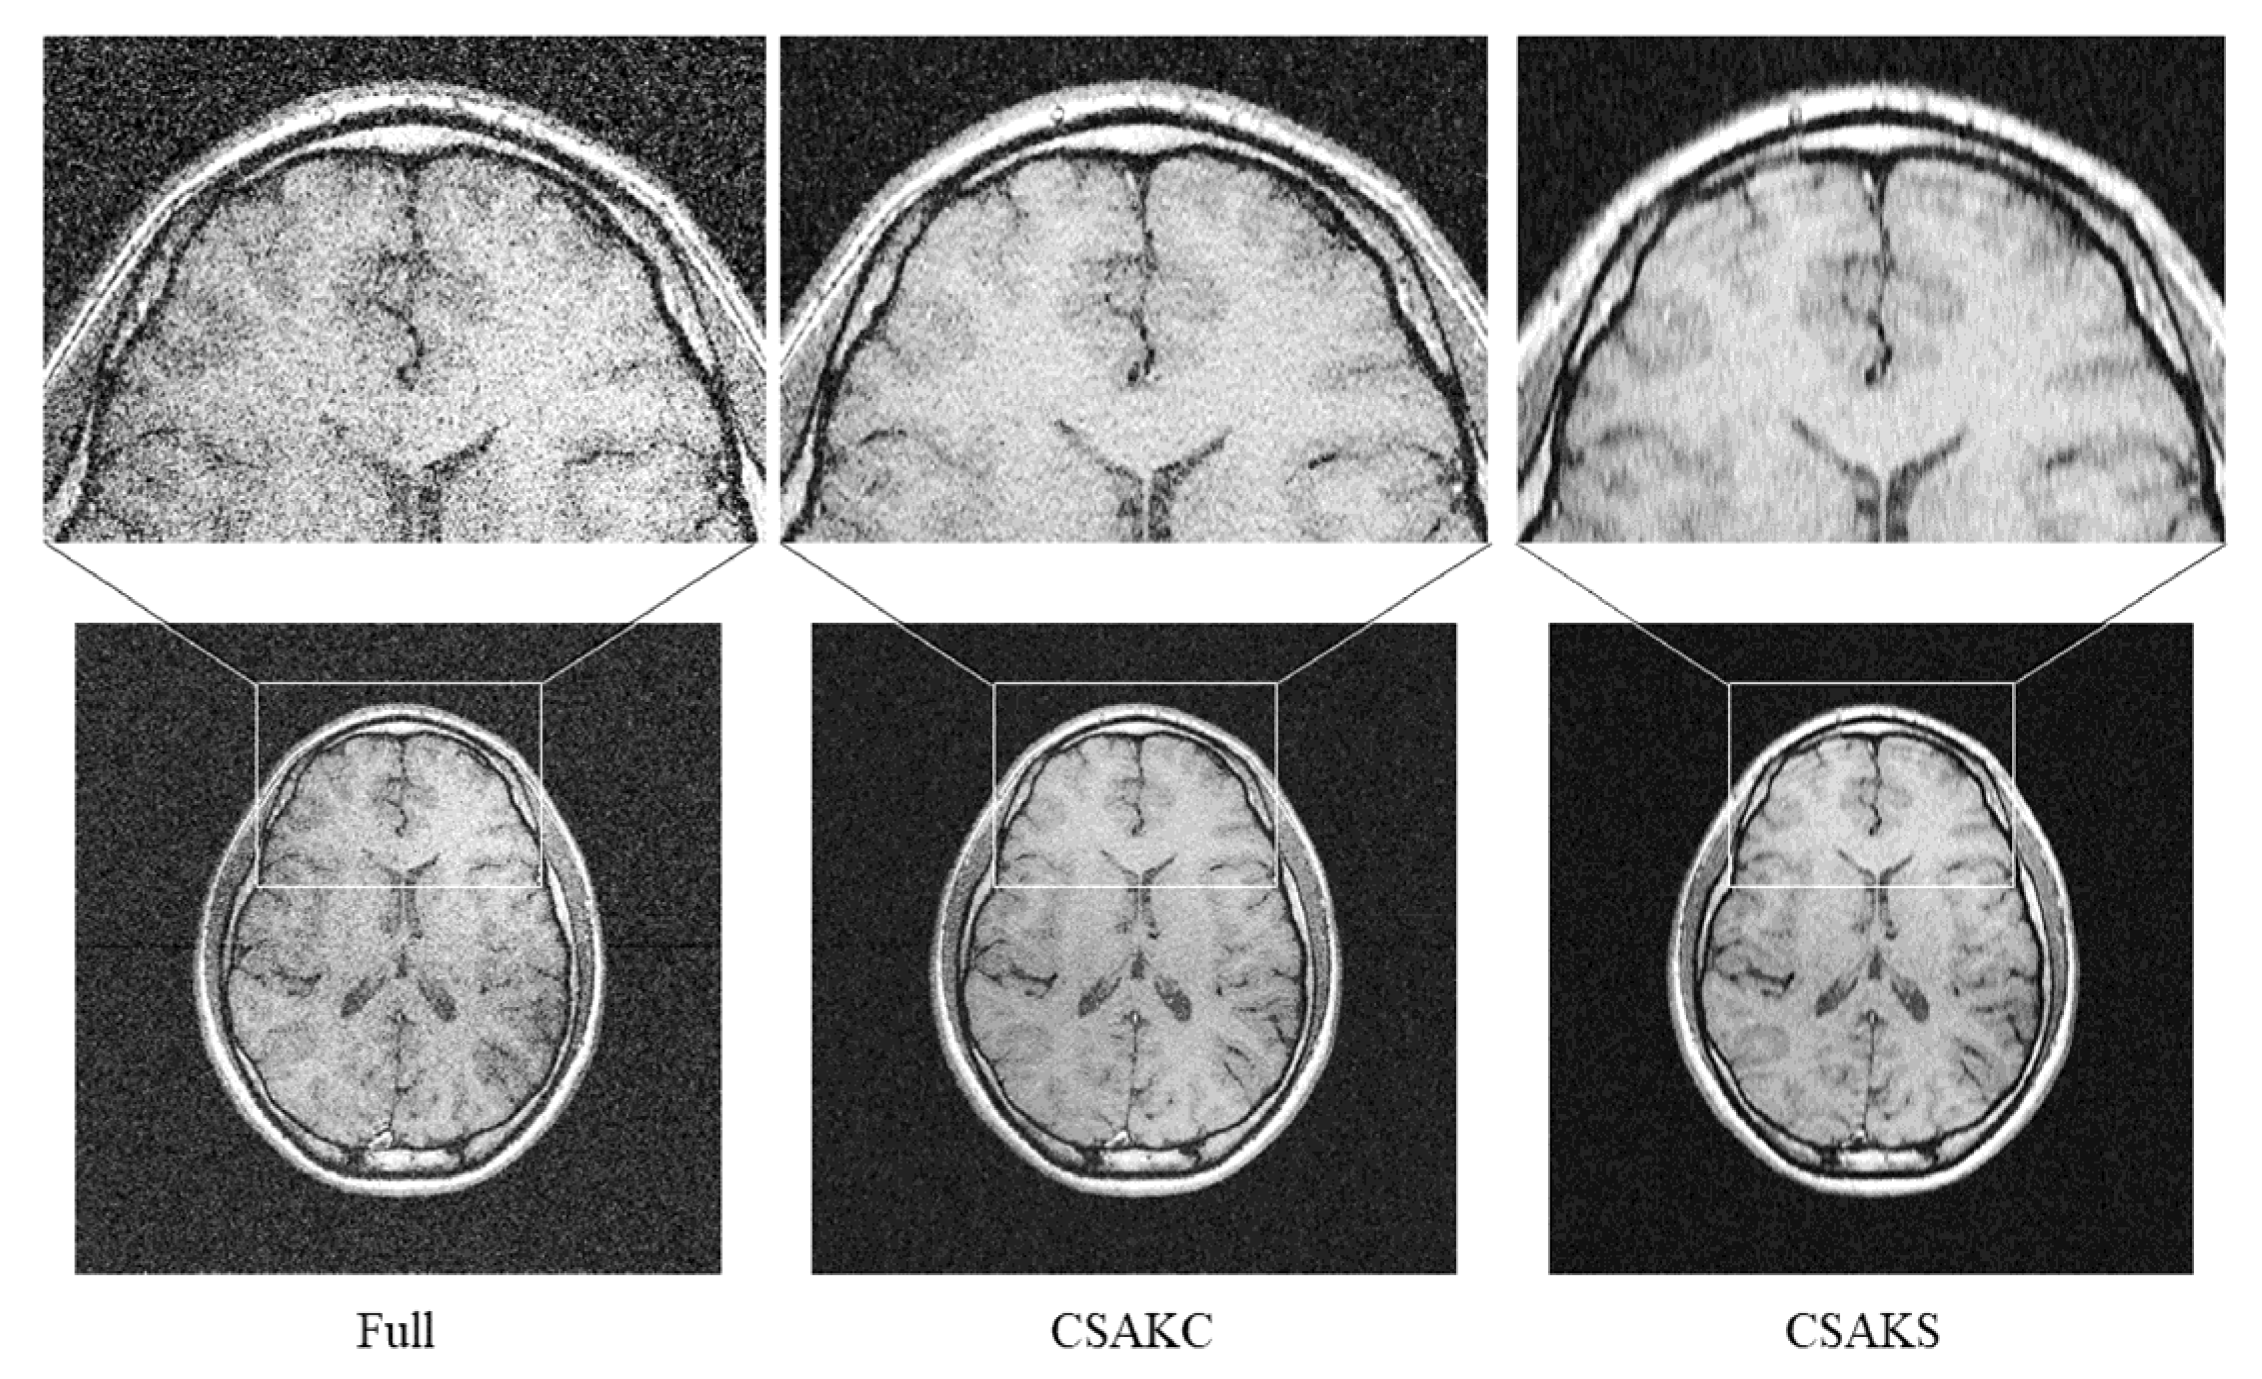

The results of the simulation performed using the full k-space sampling dataset obtained from the human participant showed that the CSA images became noisy as the undersampling ratio increased, and the SNR also decreased as the number of sampling lines increased. The SNRs in the white and gray matter regions were 10.41, 9.80, 8.86, and 5.57, and 9.69, 9.35, 8.46, and 5.59, at 25%, 35%, 45%, and 100% (i.e., full k-space sampling), respectively (Table 3). Note that the SNRs in the white and gray matter were 5.57 and 5.59, respectively, for the full k-space. In addition, it was visually confirmed that a circular ringing artifact occurred at the top of the CSAM image, which was most severe at the 25% undersampling ratio (Figure 2). Ringing and blurring artifacts were also found in the CSAM and CSAKS images, although there were some differences depending on the undersampling ratio. However, they were not found in the CSAKC image (Figure 3).

To confirm whether a similar result also occurs in the undersampling ratio acquired from the in vivo human brain, CS reconstruction (TV weight = 0.01, L1 penalty = 0.0001) was performed, and each image was analyzed for comparison. Ringing and blurring artifacts appeared most prominently in the upper part of the CSAKS image with an undersampling ratio of 25%, as in the brain phantom (Figure 5).

k 1 F O V

There were no artifacts in the full k-space sampling for in vivo human imaging, but undersampling simulation images generated from the full k-space dataset demonstrated ringing and blurring (Figure 2). Furthermore, this study also used the brain phantom to investigate whether aliasing in CSA images was an artifact caused by motion or by a lack of sampling lines. The results showed that the smaller the number of sampled lines (i.e., 25%), the greater the number of artifacts. As a result of the analysis, we found that no artifacts occurred in images with full k-space sampling, but that aliasing occurred according to the undersampling ratio even in a motionless brain phantom. This can be interpreted as the result of insufficient k-space sampling numbers, not motion. Furthermore, although CSAKC required a shorter acquisition time, it had no image blurring and a high signal intensity compared with a full k-space image (Figure 5).

Figure 5. Visual comparison of a full k-space image and CSAK images in a human subject. Although CSAK images were acquired with the same undersampling ratio, the ringing artifacts only occurred when using CSAKS. Note that the acquisition times of the full k-space and CSAK images were 5 m 56 s and 5 m 5 s, respectively.